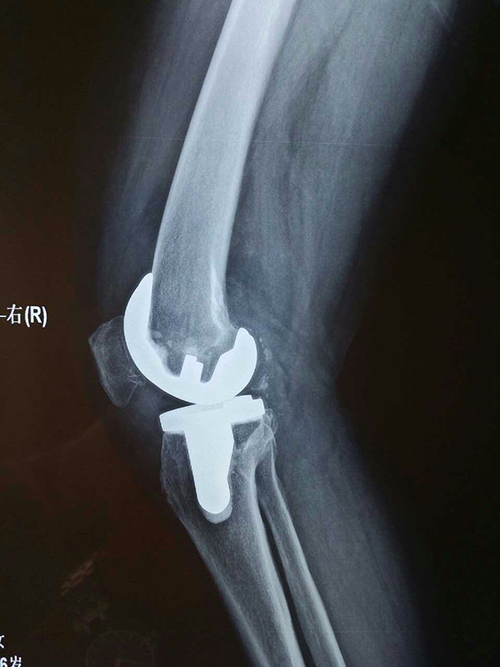

屈膝120°

伸膝0°

他告诉李主任,现在的他每天早晚可以进行两次常规的散步,路程大约4华里。汪老伸膝可达到0度,屈膝达到120度,上下楼梯正常,并且可以慢跑了!看着汪老完美的术后表现,李主任深感欣慰,他告诉我们,汪老人很热情,临走时还问他要了一些名片,说有类似病情的朋友一定要他们来找他咨询就诊。李主任说,看到自己手术的成功能够让一个又一个患者远离病痛的折磨,是他从医二十多年来一直的理想与坚持,做一名外科医生是自己最不后悔的选择,而做一名好的外科医生更是自己一生的追求!当看到患者顺利治愈康复出院时,也就是他觉得最自豪、最欣慰的时刻。